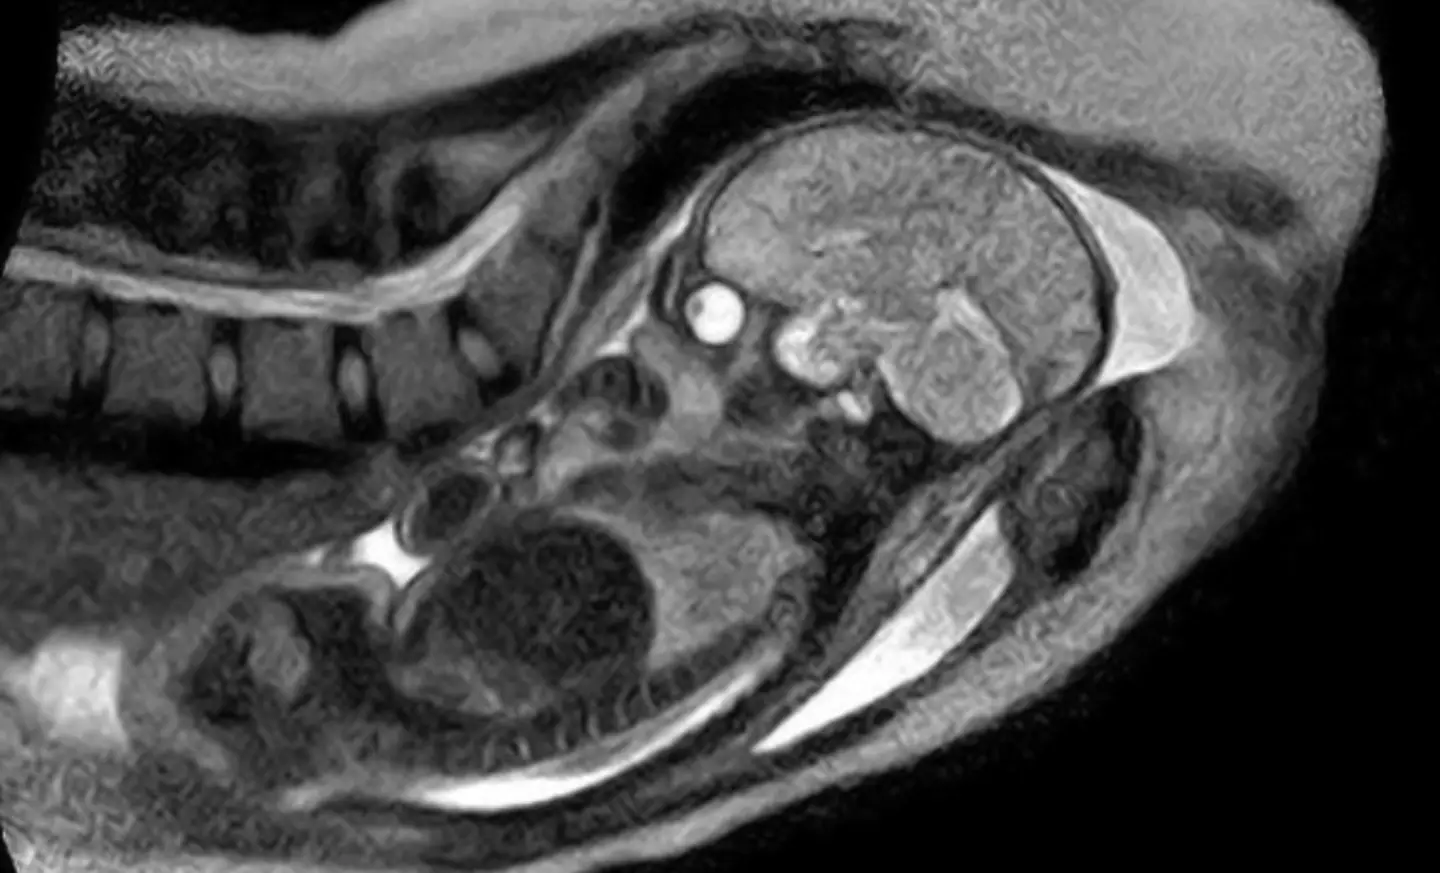

While it’s not such a ‘strange’ thing in itself, choosing an MRI scanner as the location for giving birth is rather, well, unique.

In 2010, a German woman welcomed her baby from within the machine, with 3D pictures of her womb being captured the whole time.

Amazingly, doctors could even watch how the baby’s head changed shape as they moved from the birth canal and then down the birth canal towards the entrance to the vagina.